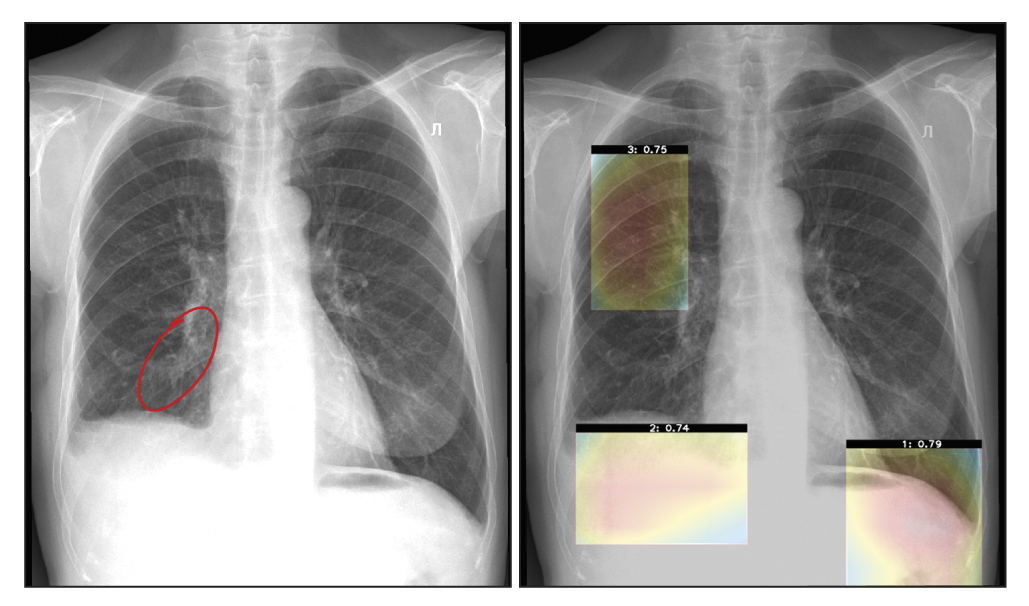

During periodic monitoring, a clinical assessment of software results is also performed by radiologists. Two main evaluation criteria include interpretation (conclusion) and localization (labeling) of an abnormal finding. During the assessment, the response options that clinicians can choose from include full compliance, incorrect assessment, false positive result, and false negative result. For example, the wording “Interpretation: Full compliance” is selected when a specialist fully agrees with the software conclusion, and the wording “Interpretation: Incorrect assessment” is selected when the doctor partially agrees with a software conclusion (e.g., the specialist agrees with the presence of abnormal findings but disagrees with its details, or vice versa, they agree with details but disagree with the general conclusion about the possibility or severity of abnormal findings). If the specialist completely disagrees with the software conclusion, the wordings “Interpretation: False positive result” and “Interpretation: False negative result” are used (Figure 10).

Fig. 10. False negative (the subsegmental atelectasis is not detected in the lower lobe of the right lung): Noncritical noncompliance with basic diagnostic requirements.